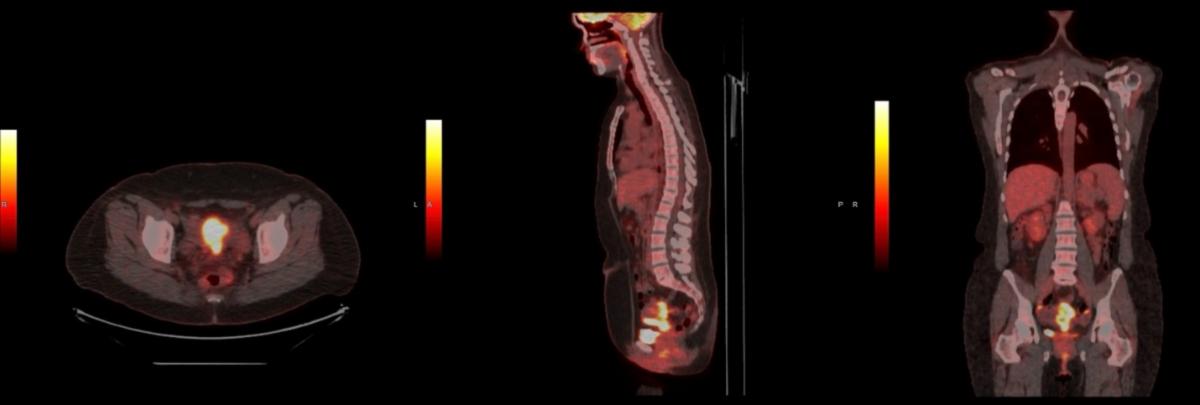

A 38-year-old woman with 1 year history of menometrorrhagia and prior abnormal Pap was found to have FIGO stage IIB moderately-differentiated, HPV-associated, cervical squamous cell carcinoma. Her disease had extensive involvement of the myometrium, parametria, and vagina without nodal involvement (Figures 1A-B). On speculum exam, the cervix was flush with the upper vagina and replaced by friable, irregular, tissue with a visible os. Bimanual exam demonstrated a 5 cm cervical mass with extension to the anterior and left vaginal fornices, and left parametrial extension on rectovaginal exam.

Given the extent of disease, she was recommended and ultimately treated with definitive external-beam radiotherapy (EBRT) and concurrent weekly cisplatin (40 mg/m2 IV) followed by four fractions of high-dose-rate (HDR) cervical brachytherapy. EBRT was delivered to the pelvis and at regional nodes to 45 Gy, followed by HDR brachytherapy, 4 fractions of 7 Gy each to the cervical high-risk clinical tumor volume (HR-CTV), delivered twice-weekly. Serial exams during EBRT showed early response. Repeat pelvic MRI in week 4 confirmed tumor response but with residual disease (Figure 2).

Figure 1A – pre-treatment PET/CT